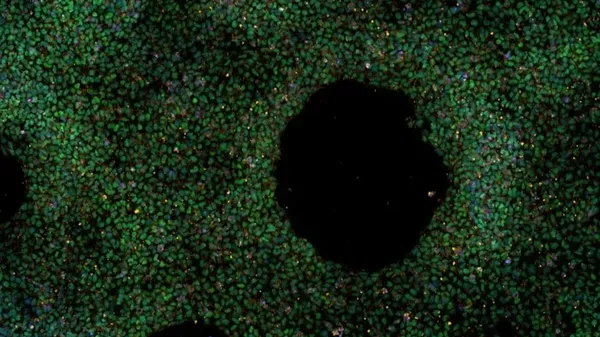

Quando le temperature salgono , il nostro orologio biologico interno è costretto a cambia re ritmo per mantenersi sincronizzato con il suo ciclo di 24 ore : l'attività dei geni coinvolti, infatti, si modifica con accelerazioni e rallentamenti che si …